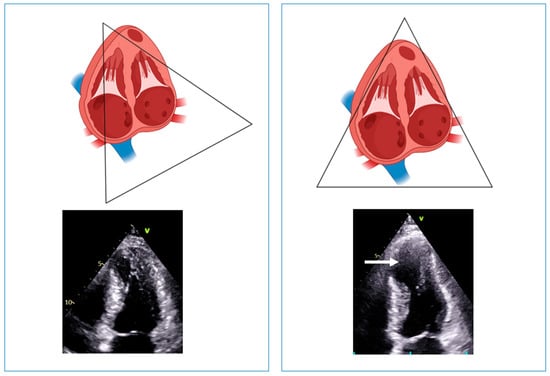

- Wigle, E.D.; Rakowski, H. Hypertrophic cardiomyopathy: When do you diagnose midventricular obstruction versus apical cavity obliteration with a small nonobliterated area at the apex of the left ventricle? J. Am. Coll. Cardiol. 1992, 19, 525–526. [Google Scholar] [CrossRef] [PubMed]

- Malcolmson, J.W.; Hamshere, S.M.; Joshi, A.; O’Mahony, C.; Dhinoja, M.; Petersen, S.E.; Sekhri, N.; Mohiddin, S.A. Doppler echocardiography underestimates the prevalence and magnitude of mid-cavity obstruction in patients with symptomatic hypertrophic cardiomyopathy. Catheter. Cardiovasc. Interv. 2018, 91, 783–789. [Google Scholar] [CrossRef] [PubMed]